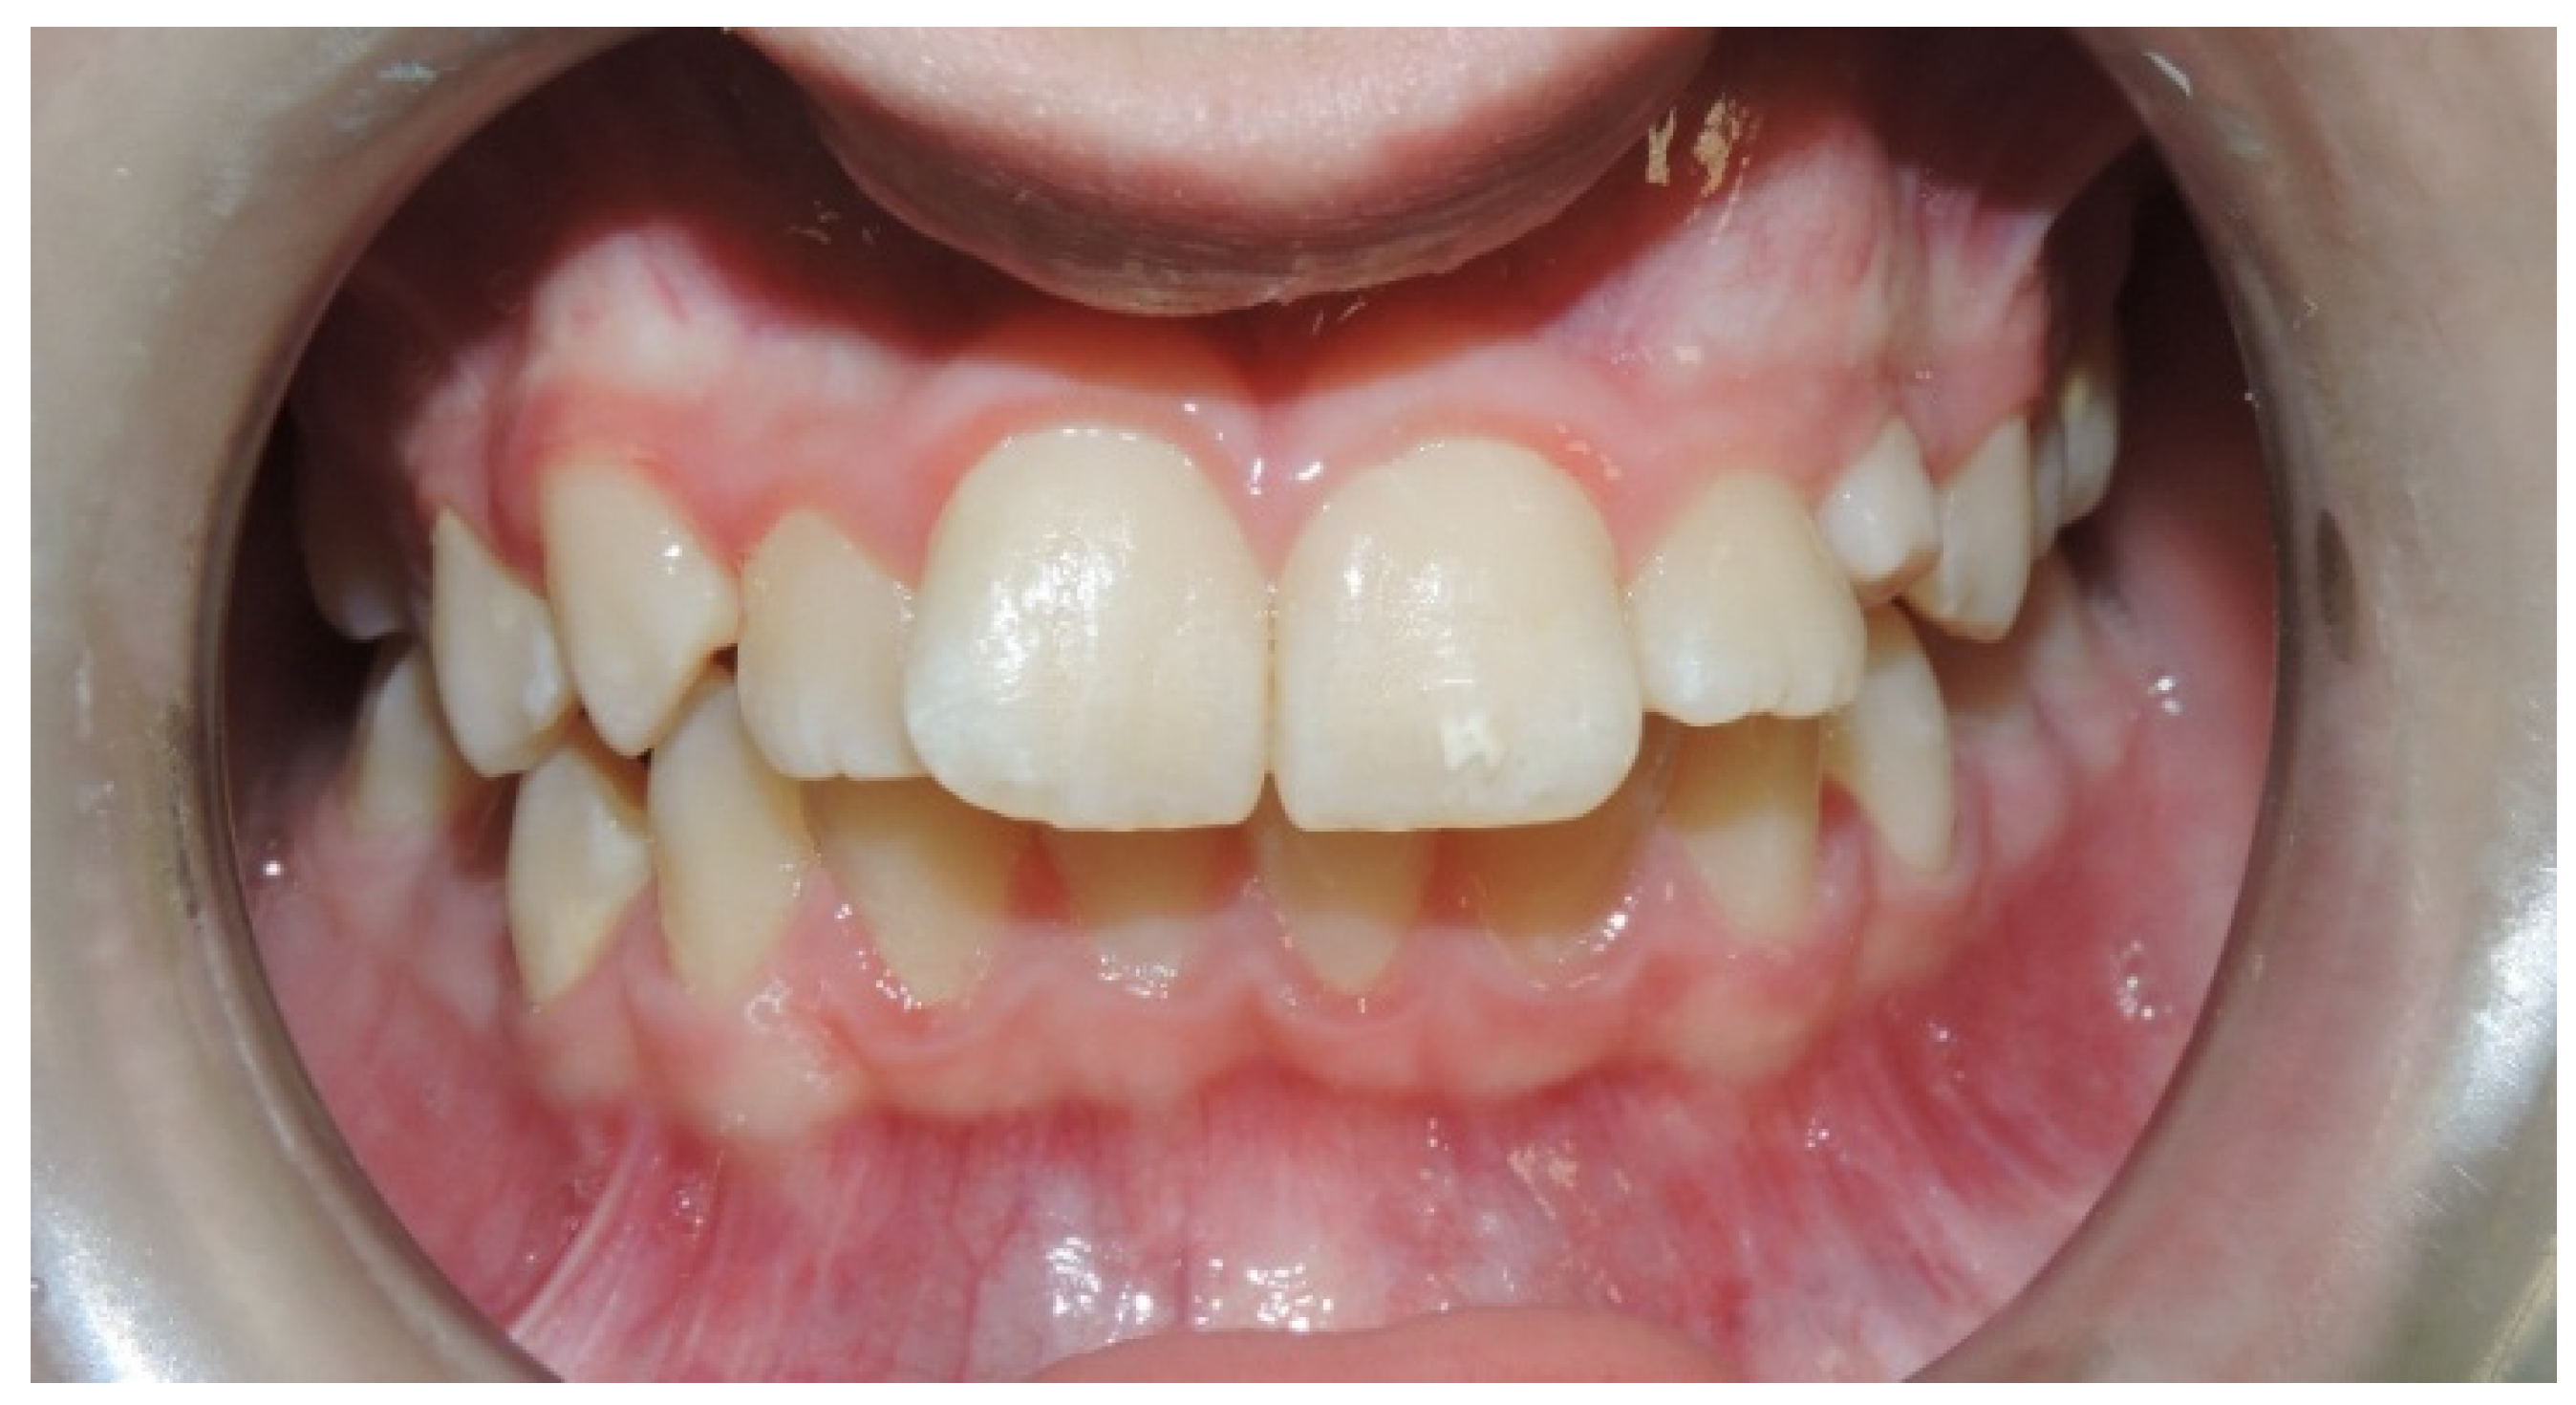

- Intra- and extra-oral photos;

- In the first step, a panoramic radiograph and a teleradiography of the skull in latero-lateral projection is required. The observation of the panoramic radiography should show the position of the impacted canine, evaluating the relationships of the canine crown with the roots of the adjacent teeth, the alpha angle, and the distance of the impacted tooth from the occlusal plane. The cephalometric study of the teleradiography should provide information about the eventually present malocclusion and treatment needed;

- Mesioinclinated Canine in Close Relation to The Root of The Lateral Incisor: In cases of vestibular canine impaction, a tight relation between the canine crown and the lateral incisor root is often visible. Every so often, moreover, the lateral incisor presents with a horizontal displacement due to the pressure of the erupting mispositioned canine. This condition frequently correlates with an increased risk of root resorption for the lateral and sometimes also for the central incisor. An orthodontic force applied on the canine crown and directed with a distal and occlusal vector could increase the probability of pressure, due to the fact of this latter component, and could therefore increase the risk of root resorption. Conventional treatment should provide a traction arm in a high position and with a horizontal force direction, thus increasing the patient’s discomfort and the likelihood of eruption in free mucosa. Complex and multidisciplinary cases are particularly prone to this difficult operating condition with wide areas of contact between roots and crowns of impacted teeth [24,25]. In any case, a previous evaluation of the disimpaction prognosis is mandatory (angulation, better if the impacted tooth is mesio-angled, α angle, and sector S of localization of the crown according to the classification of Ericson and Kuroll modified by Baccetti [22]).